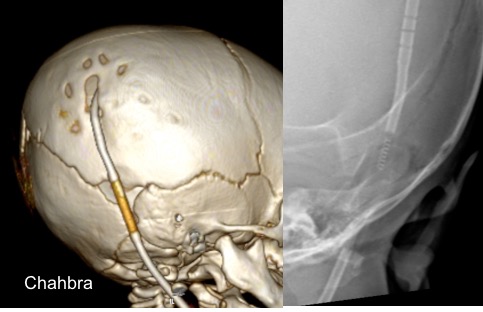

il existe un grand nombre de valves ; il n’est pas toujours aisé de les reconnaitre radiologiquement. voici la liste des plus courantes :

comment reconnaitre radiologiquement le type de valve ?